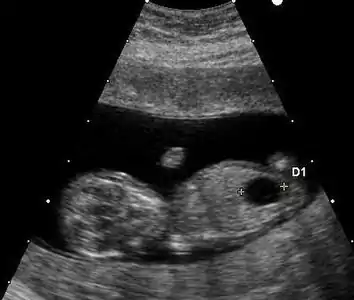

Ultrasound

Prenatal ultrasound can be used to screen for Down syndrome. Findings that indicate increased chances when seen at 14 to 24 weeks of gestation include a small or no nasal bone, large ventricles, nuchal fold thickness, and an abnormal right subclavian artery, among others.[99] The presence or absence of many markers is more accurate.[99] Increased fetal nuchal translucency (NT) indicates an increased possibility of Down syndrome picking up 75–80% of cases and being falsely positive in 6%.[100]